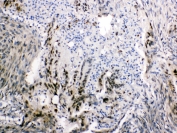

IHC staining of FFPE human small intestine tissue with I-FABP antibody (clone FABP2/7670). HIER: boil tissue sections in pH 9 10mM Tris with 1mM EDTA for 20 min and allow to cool before testing.

Applications Immunohistochemistry (FFPE) : 1-2ug/ml for 30 min at RT